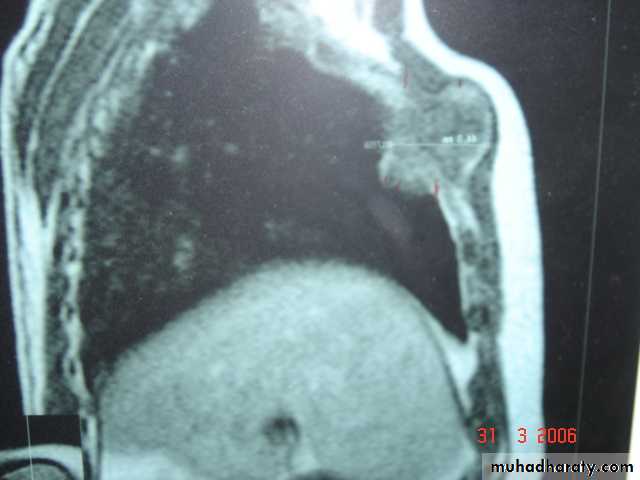

• Pulmonary Echinococcosis (Hydatid Cyst)

• Hydatid disease of the lung is caused by the small tape worm (Taenia Echinococcus ) or (Echinococcus Granulosis) .Hydatid cyst means cyst full of water .It has a life cycle between dogs & sheep .Parasites in the elementary tract of the dog shed ova that excreted in the dog faeces , contaminated the food of the sheep in which hydatid cyst will develops in the viscera . Including the lung .Infected sheep when slaughtered and its entrails are eaten by dogs , the life cycle is completed .When a human being hands or food become contaminated with canine fecal material containing ova which will be ingested .The parasitic larva burrow through the gastric mucosa and are carried to the liver in the portal venous circulation where most of them filtered out to form hydatid cyst of the liver , some escape the liver & lodge in the lung to form one or more hydatid cyst which grows slowly or rapidly over years .

• The cyst consists of a germinal layer & cyst fluid containing broad capsule & scoleses . A cellular white hyaline layers are laid down outside the cyst so that the cyst is enclosed by a laminated cyst membrane .As the cyst enlarged , it usually reaches the pleural surface . Compression of the lung tissues produces a thin fibrous layer of atelectatic lung tissue around the cyst (capsule , pericyst or adventia)

• Radiological Findings

• 1-Smooth homogenous opacity (Intact H.C).• 2-Partial rupture (per vesicular pneumocyst).

• 3-Complete rupture (Water –lilly sign) .

• 4-Formation of lung abscess(Air –fluid level) .

• 5-Completely coughed out cyst(empty cavity )

• 6-Rupture into the pleura (hydropneumothorax)